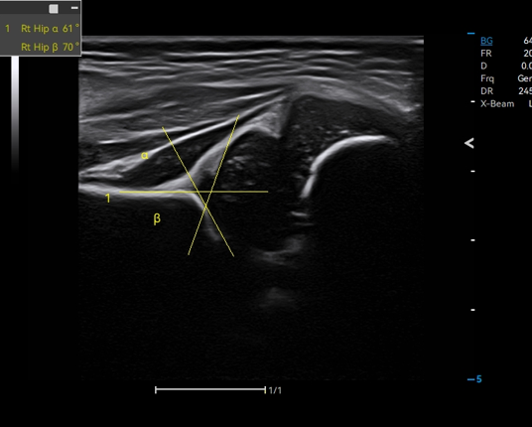

Auto Hip identifies the baseline, tracks the top line of bone and cartilage, and measures crucial results for hip dysplasia evaluation.